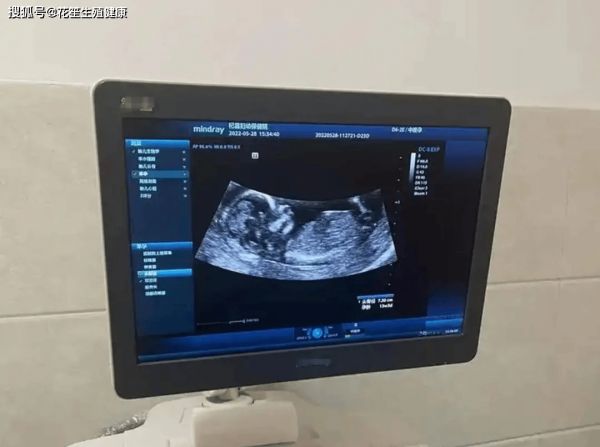

胚胎移植那天下着太阳雨,实验室的显微镜屏幕里,那个跃动着的小光点像坠入凡间的星子。医生指着显示屏说:"看,它正在对着你们眨眼睛呢。"回家后我平躺了整整三天,连翻身都像在拆解炸弹,丈夫把饭菜做成迷你寿司,说这样我不用抬头就能吃到。直到第十四天验孕棒浮现两道粉线,我们才发现阳台的茉莉不知何时结满了花苞,晨露在花瓣上滚动,像极了显示屏里那个"眨眼睛"的小生命。

如今每次产检听到胎心仪里的"小火车"声,都会想起促排期间那些自己给自己打针的深夜。冰凉的酒精棉擦过肚皮时,窗外总有夜班护士推着治疗车经过,轱辘声与我的心跳形成奇妙的二重奏。原来生命最动人的乐章,往往诞生于最寂静的黑暗里。